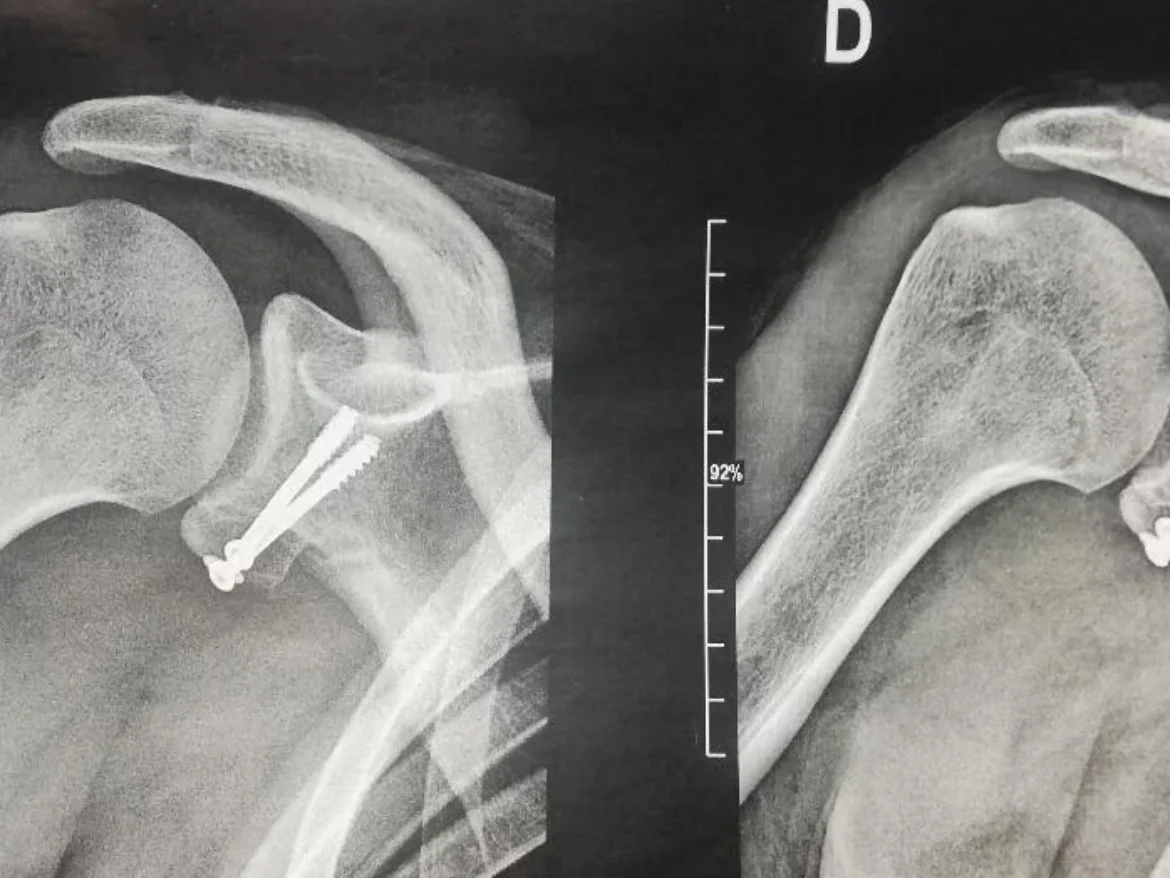

LUXATION ACROMIOCLAVICULAIRE

En savoir plus